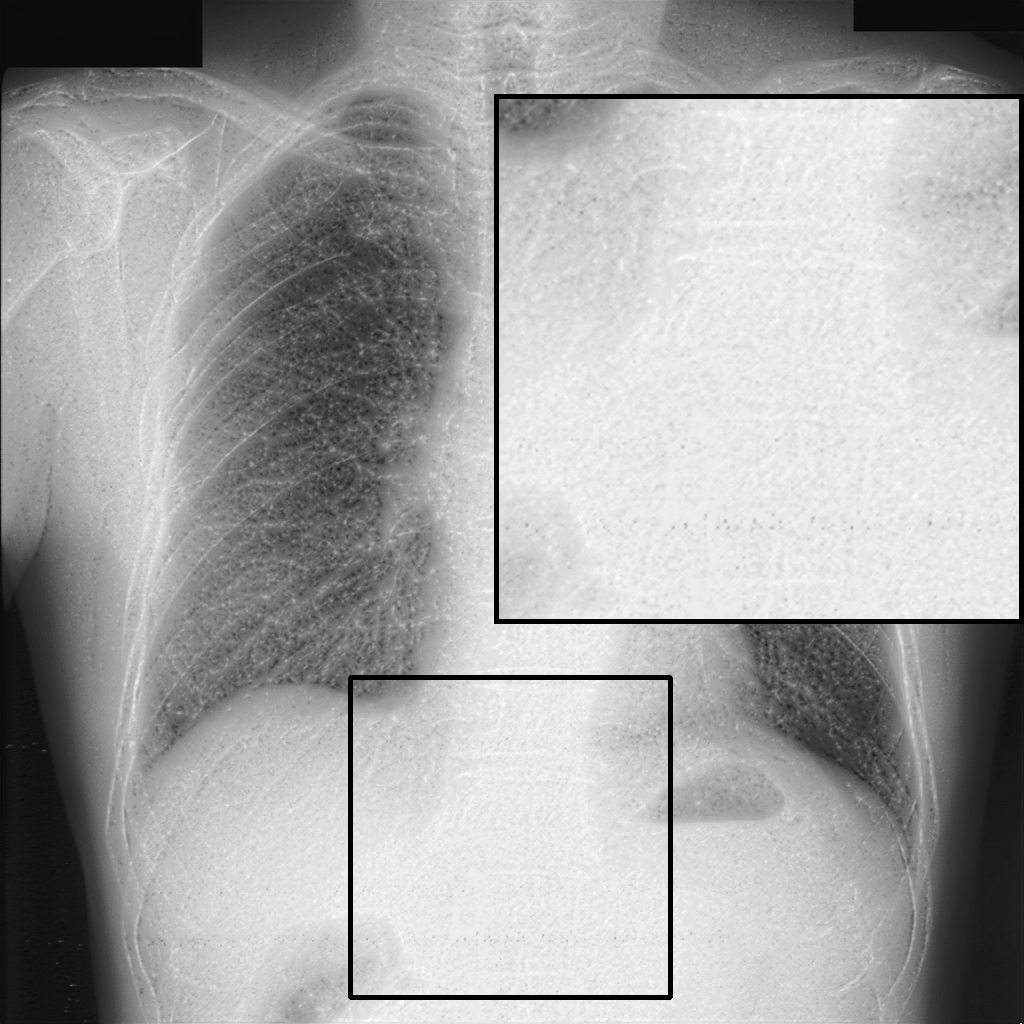

4.7.1 GL Effect

To evaluate the GL’s impact, we conducted an ablation study by comparing model outputs with and without the GL after two training sessions (see Table 3). The results, reported as mean ±\pm standard deviation, demonstrate that the GL significantly improves image sharpness and perceptual quality, as reflected by higher TC, LPC-SI, and TMQI scores. The PIQE score also shows a dramatic decrease when the GL is included, indicating a reduction in perceptual image distortion. In contrast, entropy values remain comparable, suggesting a similar pixel distribution regardless of the presence of the GL.

Statistical analysis using the Wilcoxon rank test (applied to scores within the range of mean ±\pm 1.96 standard deviations) confirms the significance of improvements in TC, LPC-SI, TMQI, and PIQE (p<0.05p<0.05). Interestingly, the model without GL exhibits significantly higher entropy (p<0.05p<0.05), although this metric alone does not necessarily indicate superior structural or perceptual quality. Furthermore, gradient map visualizations (see Fig. 5) provide additional insight into the GL’s contribution, revealing clearer object outlines and finer details in comparison to settings without the GL.

Overall, the ablation study underscores the substantial role of the GL in enhancing image quality, particularly in terms of TC, LPC-SI, and TMQI, as supported by both quantitative measures and qualitative visual evidence.

Refer to caption

(a)

(b)

(c)

(d)

(e)

Figure 5: Visualization of gradient maps: (a) Original image fragment, (b) gradient of the original fragment, (c) gradient with single HFC as guidance, (d) gradient without GL, and (e) gradient with GL